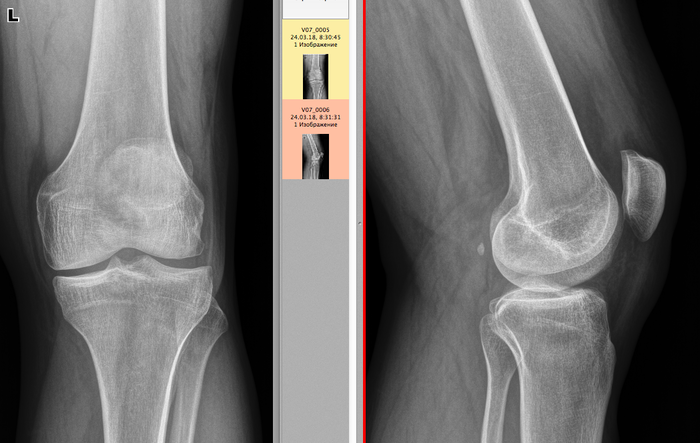

История 4. Синовиальный остеохондроматоз

Синовиальный хондроматоз (синдром Лотша, коралловый сустав) относят к группе костных и хондроматозных новообразований. Это сравнительно редкое, длительно прогрессирующее доброкачественное заболевание, характеризующееся образованием множества хрящевых новообразований – хондроманозных телец в толще синовиальной оболочки суставной сумки, которые в дальнейшем отделяются в суставную полость и обызвествляются.

Хондромы возникают изнутри синовиальной оболочки как скопления хрящевых клеток, которые растут, выпячиваются в полость сустава, приобретают ножку. В конце концов ножка обрывается и хондрома (остеохондрома) оказывается свободным телом, продолжающим расти, увеличиваясь в размере. Когда в суставе только одно или два свободных тела, то первым симптомом может оказаться блокада сустава.

Вспомним, как выглядит сравнительно здоровый коленный сустав:

А теперь к вышеописанному заболеванию. Мужчина, 60 лет, в анамнезе множественные травмы коленного сустава (разрывы связок, переломы). В проекции супрапателлярной сумки две высокоинтенсивные тени овальной формы, с неровными, четкими контурами, неоднородной структуры, размером 45х16 и 32х17 мм.

Нижней стрелочкой указан выраженный артроз коленного сустава 3-4 ст.